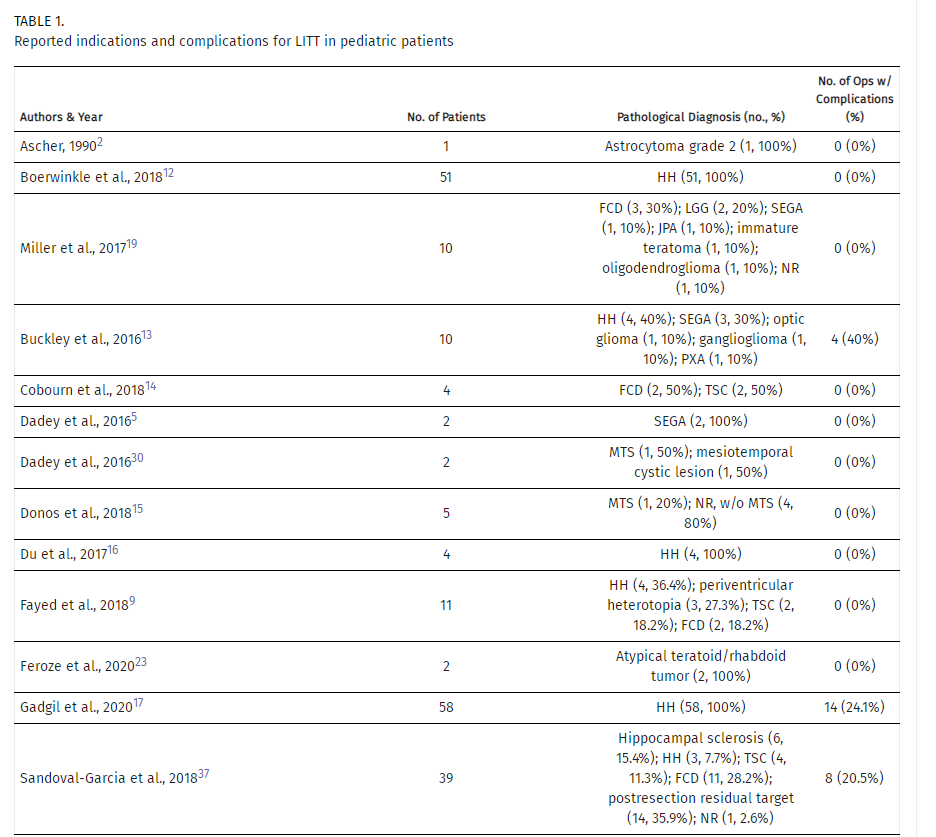

表2:儿科患者与LITT相关的并发症的频率和类型

尽管LITT是一种微创手术,但并发症仍在普通人群中发生,在一项全国性研究中,并发症发生率为12.9%,死亡率为2.5%。神经功能缺损是LITT术后最常见的并发症,通常是LITT高热和消融后水肿的直接结果。在上述研究中,报告了9例局灶性神经功能缺损,其中偏瘫和视野缺损最为常见。其他神经系统并发症包括9例认知障碍报告和4例癫痫恶化。大多数认知障碍,最常见的是短期记忆丧失,见于下丘脑错构瘤患者。短期记忆丧失一直是下丘脑错构瘤手术后最常见的并发症之一,与治疗方式无关。在总的神经系统并发症中,77.3%是短暂的,这与文献报道的LITT后不良事件很少导致永久性神经系统发病率相一致。

值得注意的是,技术并发症占本综述报告并发症的18.2%(n=10)。这是导管放置不理想和装置技术困难的结果,导致出血和无效消融,需要再次手术。在上述研究的5例导管错位和1例装置故障中,没有一名患者出现持续的并发症。尽管如此,手术并发症的最小化将带来更有效的治疗,并减少更具侵入性的手术的必要性。